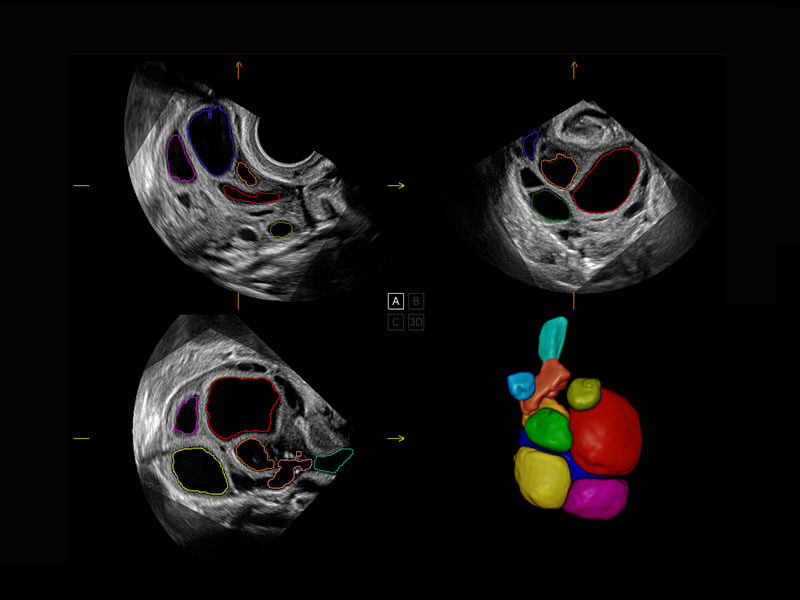

S-Fetus能够助您在实时扫查过程中自动识别标准切面、自动测量并录入报告。一个按键,即可快速、高效地获取胎儿生理指标,简化您的产科检查操作。

1 OFD(HC): 87.03 mm

HC: 251.00 mm

GA: 27w 1d

HC/AC: 96.13 %

2 BPD: 70.56 mm

GA: 28 w 2d

S-Fetus(acq.)

&

S-Fetus(meas.)